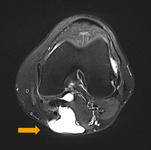

MRI depicting cyst in interval of medial gastrocnemius and semimembranosus

From the collection of Dr John D. Kelly IV; used with permission

A ruptured haemorrhagic popliteal cyst extending in the calf

Stony Brook University Medical Center private collection; used with permission

Preoperative T2-weighted MRI showing posterior fluid collection communicating with posterior medial joint in a patient with a popliteal cyst secondary to pigmented villonodular synovitis

Adapted from Tosti R, Kelly JD 4th. Pigmented villonodular synovitis presenting as a Baker cyst. Am J Orthop (Belle Mead NJ). 2011;40:528-531; used with permission